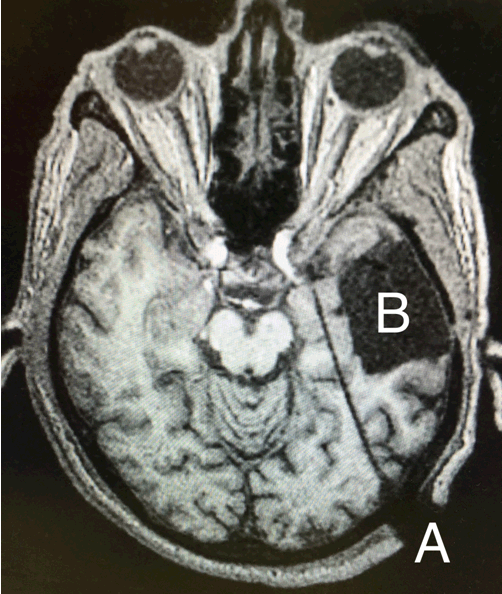

The patient underwent a preoperative volumetric MRI for stereotactic navigational purposes. The patient was placed under general anesthesia and then placed in a lateral position. We used the ROSA robot (MedTech Surgical, Inc, Montpellier France) to assist with implantation of a laser cannula through a transoccipital approach to the mesial temporal lobe. The patient was placed in a Leksell stereotactic head frame (Elekta, Crawley, United Kingdom) to connect him to the robot (i.e., not for stereotactic navigational purposes). Additionally, bone fiducials were used because facial registration is less accurate when the patient is in the lateral position. A mesial temporal trajectory was planned with the ROSA navigation software, including the entry point and trajectory needed to reach the target (Figure 1). A percutaneous burr hole was made on the scalp at the entry point and a PMT skull bolt (PMT Corporation, Chanhassen, Minnesota) was placed in the correct trajectory. We passed a cannula through the skull bolt and advanced it to the predetermined depth (Figure 2). The laser applicator was then placed within the cannula and secured. The patient was then transported to the MRI suite for the remainder of the procedure. Imaging confirmed correct placement of the laser applicator and then the LITT commenced.

Figure 2: Axial image of the trajectory of the laser applicator taken from the posterior aspect of the head to the mesial temporal lobe; (A) Entry point, and (B) Cavitation.